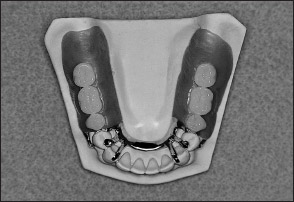

A Class II removable partial denture must embody features of both Class I and Class III designs (Fig 1-41). The unilateral distal extension side must be designed as a Class I removable partial denture, whereas the tooth-supported side must be designed as a Class III removable partial denture. The prosthesis must include a well-adapted denture base, properly designed direct retention, and appropriately positioned indirect retention.

Fig 1-41 Representative Class II removable partial denture (Kennedy Class II, Modification 1).